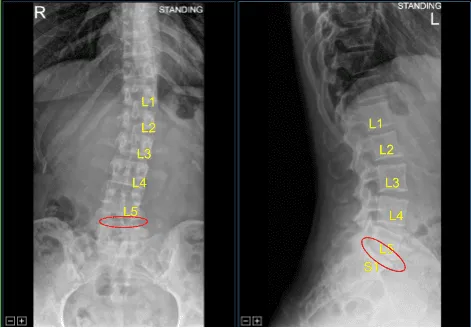

El paciente acudió a la clínica de neurocirugía con signos y síntomas de espondilosis lumbar y radiculopatía a nivel L5-S1 de la columna lumbosacra. No tomaron medidas conservadoras extensas y se recomienda cirugía para descomprimir y estabilizar la columna lumbar.

Degeneración discal moderada